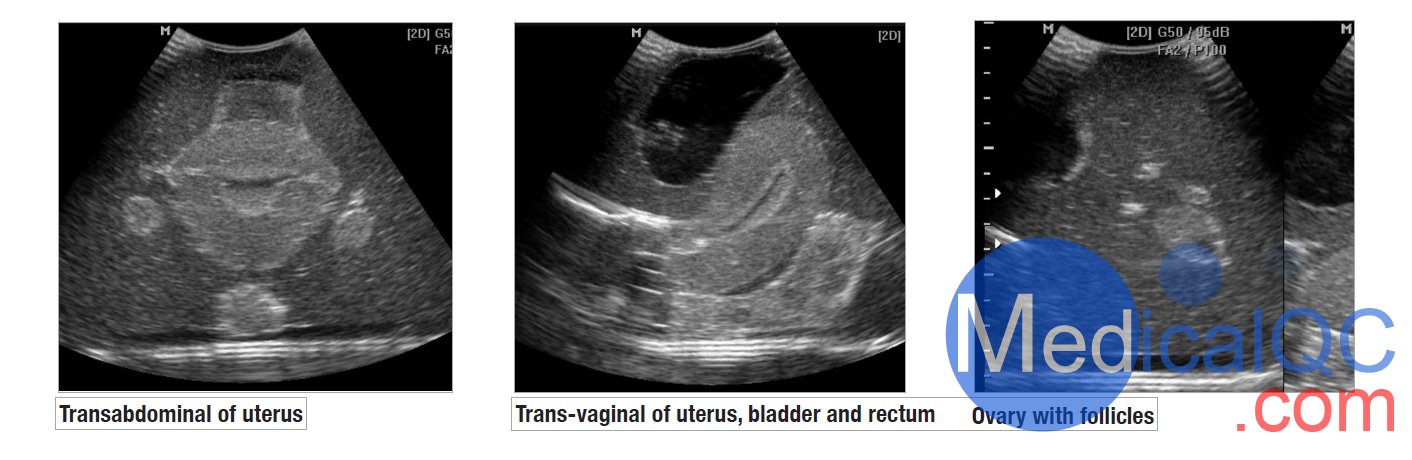

CIrs 404A女性盆腔模體,CIrs 404A超聲訓(xùn)練骨盆模體超聲影像圖:

CIrs 404A女性盆腔模體,CIrs 404A超聲訓(xùn)練骨盆模體影像圖

我們的CIrs 404A女性盆腔模體,CIrs 404A超聲訓(xùn)練骨盆模體由一個(gè)外部女性盆腔模型組成,其中包含用于掃描的子宮、輸卵管、卵巢、膀胱和直腸標(biāo)志。體模具有腹部和陰道掃描通道,允許各種換能器方向。

CIrs 404A女性盆腔模體,CIrs 404A超聲訓(xùn)練骨盆模體是一種重要的診斷工具。學(xué)生通過動(dòng)手實(shí)踐獲得能力。不幸的是,接觸患者可能受到限制。CIrs 404A女性盆腔模體,CIrs 404A超聲訓(xùn)練骨盆模體有助于在無壓力情況下教授和演示婦科超聲技術(shù)。

女性超聲訓(xùn)練骨盆為教授和發(fā)展超聲檢查技能和技術(shù)以及展示 3D 超聲能力創(chuàng)造了一個(gè)輕松的學(xué)習(xí)環(huán)境。